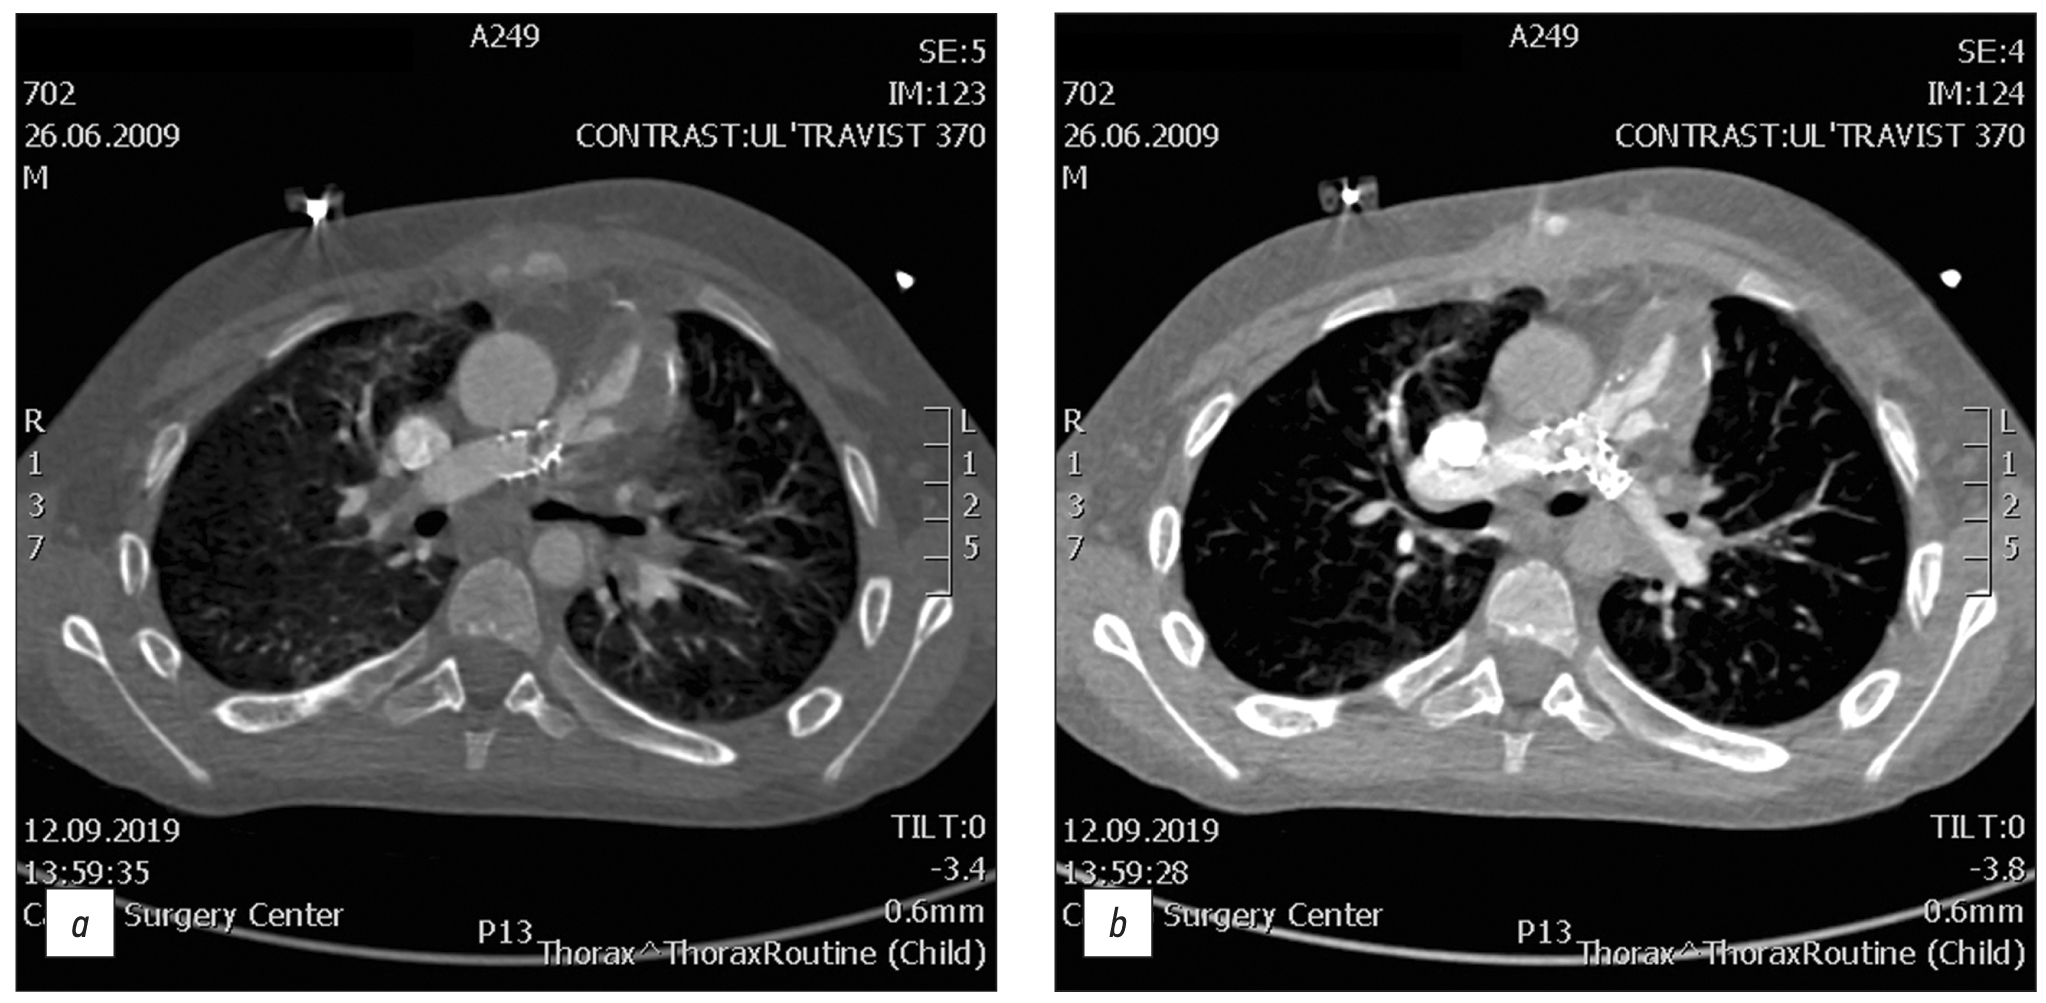

Frequency of various cardiac complications in children with repaired tetralogy of Fallot identified by computer tomography

Resumo

BACKGROUND: Tetralogy of Fallot represents 7–10% of all cases of congenital heart disease, as it occurs in approximately 0.5 per 1,000 live births and is the second most common form of complex congenital heart disease. Advances in diagnosis, surgical techniques, and postoperative treatment have led to an increasing number of patients reaching adulthood, with a dramatic increase in the survival rate to almost 90% at 30 years, thereby creating a need for long-term monitoring of certain anatomic parameters to identify complications in a timely manner. This study aimed to investigate the frequency of computed tomography detected complications after radical correction of Tetralogy of Fallot in pediatric patients.

AIM: to identify markers between the most frequency computed tomography detected complications after repair of Tetralogy of Fallot in pediatric patients.

MATERIALS AND METHODS: A retrospective analysis was conducted on 613 patients with Tetralogy of Fallot from October 2011 to June 2020. The study included a total of 116 patients (69 men and 47 women) who experienced complications after a repair of Tetralogy of Fallot, as identified by computed tomography. At the time of repair of Tetralogy of Fallot, the patient’s average age ranged from 10 to 36 months (mean: 12 months), average body weight was 21 kg, average height was 105.4 cm, and average body surface area was 0.74 m2. The patients’ median age at the time of the computed tomography examination was 17.5 years (age range: 7–36 years).

RESULTS: Among the 116 patients who exhibited complications after an repair of Tetralogy of Fallot, 49 had a pulmonary artery stenosis, 92 had a pulmonary artery branch stenosis (56 of them of the left main pulmonary artery branch, and 36 of them of the right main pulmonary artery branch), 8 had a right ventricular outflow tract stenosis, 32 had a ventricular septal defect, 1 had a shunt thrombosis, 12 had a postoperative deformation of the pulmonary artery, 10 exhibited a marked right ventricular dilatation, 2 had an right ventricular outflow tract aneurysm, and 6 suffered from conduit calcification and stenosis. Moreover, patients with left main pulmonary artery branch stenosis had a 6.5 times greater chance of developing an right main pulmonary artery branch stenosis in (p <0.001).

CONCLUSION: The most frequently computed tomography detected complications after a repair of Tetralogy of Fallot were pulmonary artery stenosis and pulmonary artery branch stenosis. Patients with pulmonary artery stenosis and pulmonary artery branch stenosis exhibit no significant differences in terms of age, anthropometric parameters (height, weight, and body surface area), and gender distribution in the presence or absence of different stenosis types (pulmonary artery, right main pulmonary artery branch, or left main pulmonary artery branch). However, an right main pulmonary artery branch stenosis increases the chances of developing an left main pulmonary artery branch stenosis.

268-279